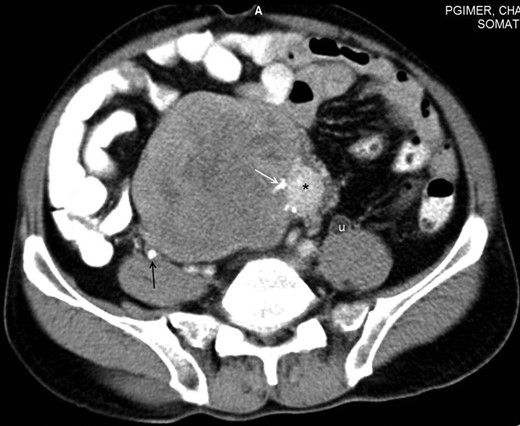

A 48-year-male patient presented with awareness of gradually increasing lower abdominal lump and abdominal discomfort for 8 months. There was no history of anorexia and weight loss. He was a non-smoker and non-alcoholic. His general physical examination was unremarkable with no clinical evidence of hepatic disease and adrenal or pituitary insufficiency. On abdominal examination, about 8 × 10 cm non-tender, hard, well-defined intra-abdominal lump was present in hypogastrium, which was extending into right iliac fossa, right lumbar and umbilical region for which the lower margin was not palpable. The lump was bimanually palpable on rectal examination. It was causing intra-luminal projection within rectum without any mucosal irregularity. His initial basic laboratory investigations which included hemogram, coagulogram, blood sugar, serum sodium, potassium, chloride, calcium, renal and liver function tests and urine analysis were within normal range. CECT abdomen (Figs 1 and 2) revealed a 20 × 15 × 7 cm heterogenous well-defined lobulated mass with calcification and areas of necrosis in the pre-sacral region and was extending superiorly up to the lower border of L3. It was indenting into the bladder anteriorly and rectum posteriorly, also abutting pelvic vessels but maintaining fat planes with all these structures. This mass was causing bilateral hydroureteronephrosis.

Axial section of contrast-enhanced CT of the abdomen reveals a large heterogeneously enhancing mass with a small hyperenhancing component (asterisk). Foci of calcification are noted within the lesion (white arrow). A few hypoenhancing areas are also seen within the lesion, which might represent necrosis or scar formation. Incidentally, a ureteric calculus is seen on the right side (black arrow). Dilated ureter (u) is noted on the left side due to compression by the mass lower down. Note that the fat planes with the bowel and the retroperitoneal vessels are maintained.